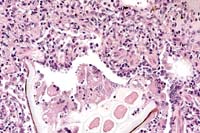

Case 27-4a. Lung. A bacterial colony and many neutrophils are plugging a small artery. and the neutrophils are transmigrating the vessel wall (bacterial embolus with necrotizing vasculitis) into the adventitia and interstitium. 40X

Case 27-4b. Lung. Foreign (plant) material plugging a bronchiole is accompanied by multinucleated giant cells. 20X

1. Multifocal, suppurative, pulmonary vasculitis and thrombosis with intralesional gram positive cocci.

2. Multifocal, granulomatous pneumonia with birefringent foreign material.

1. Lung: Pneumonia, necrosuppurative, embolic, multifocal, moderate, with necrotizing vasculitis, fibrin thrombi, and numerous cocci, rhesus monkey (Macaca mulatta), primate.

2. Lung: Bronchopneumonia, granulomatous, multifocal, moderate, with foreign material.

Conference Note: Conference participants discussed the importance of recognizing that two distinct processes are evident. One process is chronic, bronchocentric, and a result of foreign material introduced into the airways. The other process is more acute, angiocentric, and a result of staphylococcal bacteremia.